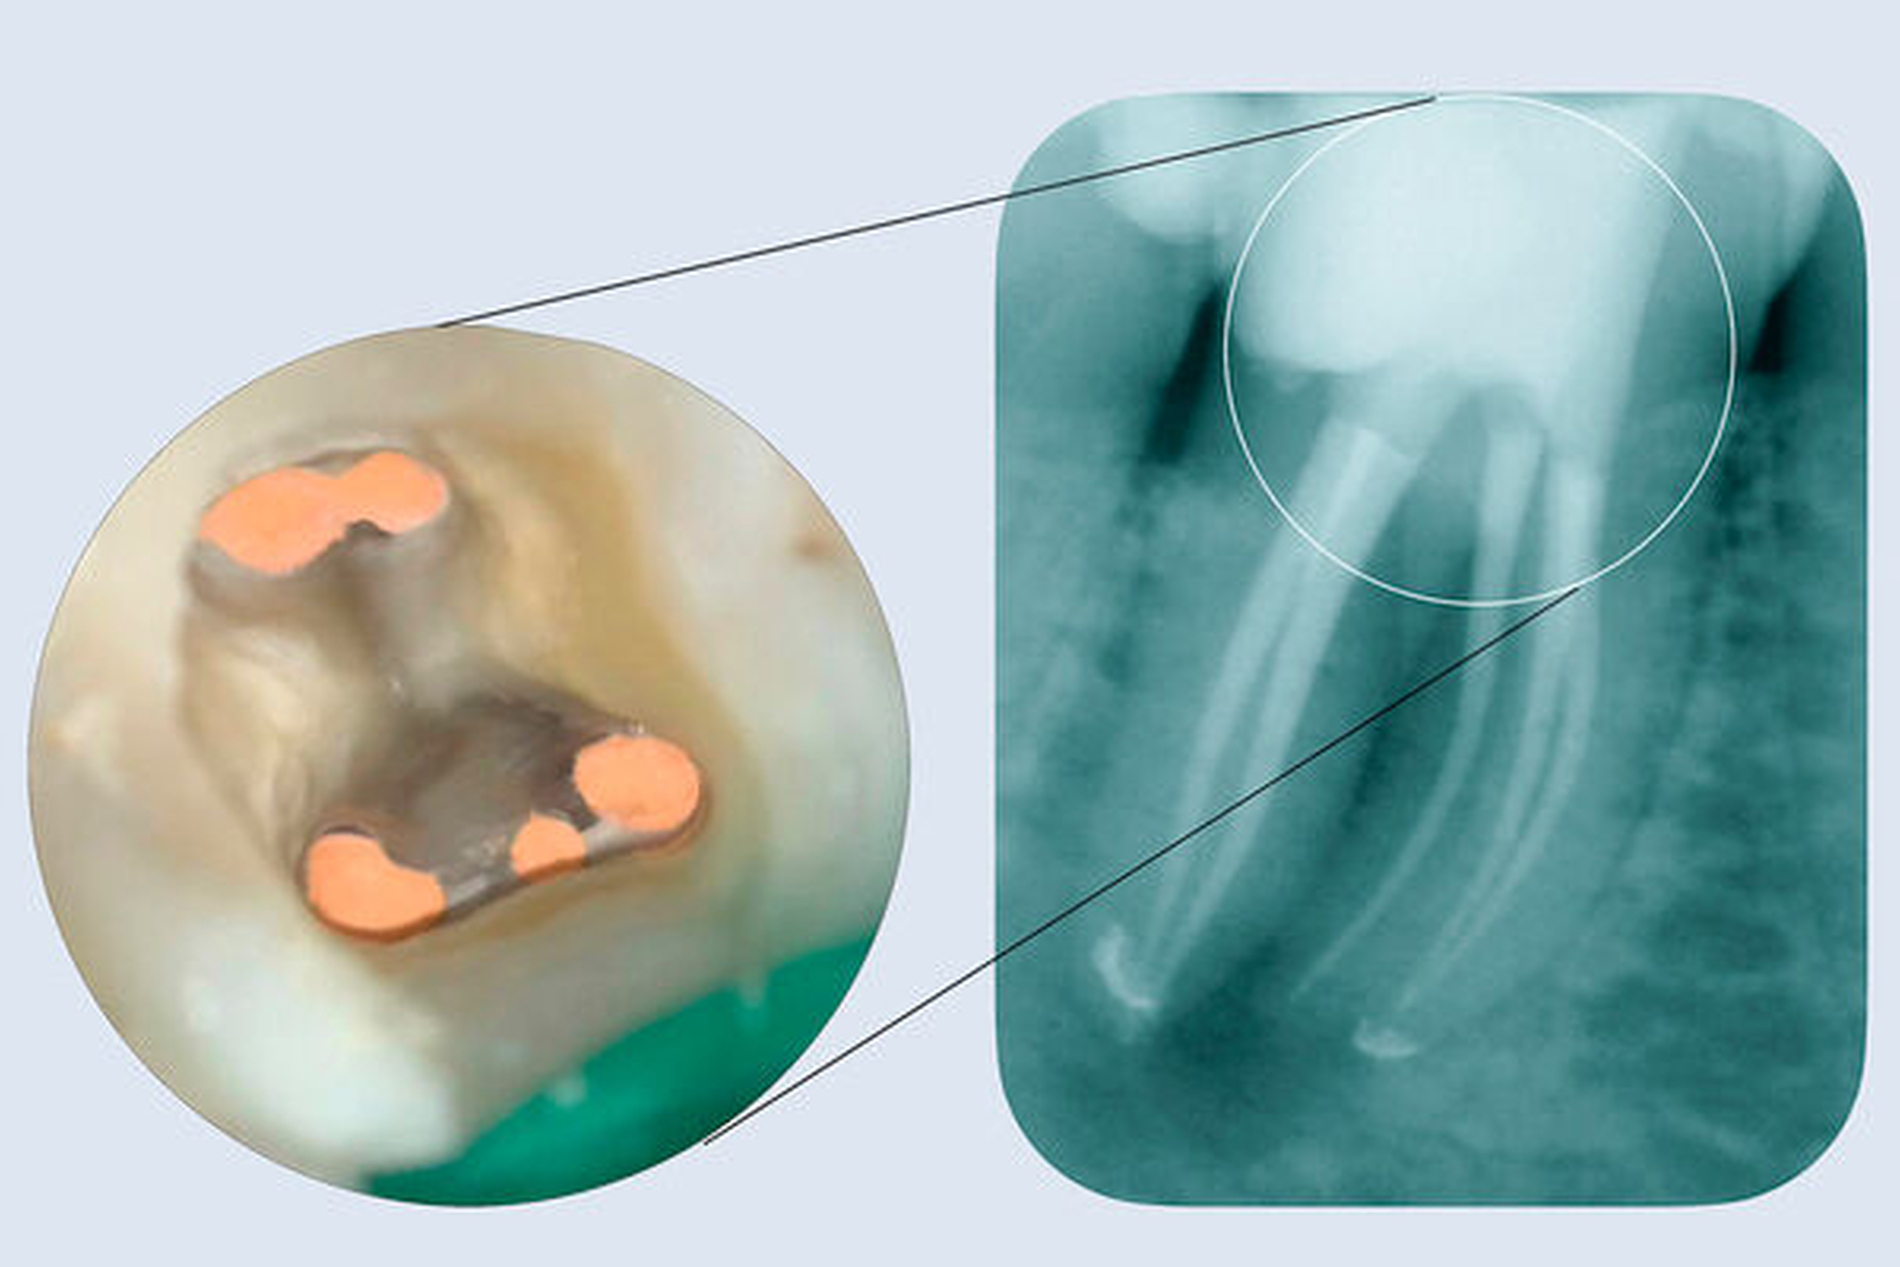

Der radiologische Befund ergab im Zahnfilm (Abbildung 1A) eine apikale und interradikuläre Aufhellung. Die Anfertigung einer Low-Dose-DVT-Aufnahme zeigte eine teilweise Resorption der bukkalen Kortikalis und der interradikulären Spongiosa sowie eine Erweiterung des Parodontalspalts nach koronal über das mittlere Wurzeldrittel hinaus. Die virtuelle Darstellung der Wurzelkanalverläufe zeigte fünf Wurzelkanaleingänge und fünf Wurzelkanalausgänge (Abbildung 1 B).

Nach erfolgter Aufbereitung und Desinfektion aller Wurzelkanalabschnitte wurde der Zahn verschlossen (Abbildungen 1C und 1D). Auf die systemische Gabe von Antibiotika wurde aufgrund der lokalen Symptomatik und des fieberfreien Zustands der Patientin verzichtet. Nach sieben Tagen waren die Symptome rückläufig. Nach einer erneuten Eröffnung und Desinfektion erfolgten fünf thermoplastische Wurzelkanalfüllungen mit nachfolgender Composite-Restauration und anschließender radiologischer Kontrolle.